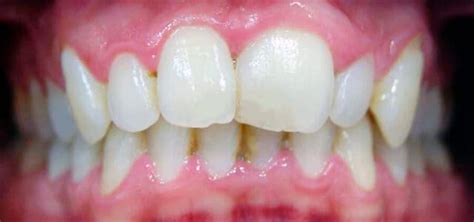

Una poco común pero muy visible a la vista es la microdoncia dental, una condición que puede tener un impacto significativo en la forma y tamaño de los dientes. Se trata de una alteración en la que los dientes son bastante más pequeños que el resto de elementos de la boca. La raíz de de la pieza dental puede ser de tamaño normal, pero las coronas son más pequeñas.

La microdoncia es una alteración dental en la cual los dientes son más pequeños de lo habitual. Esta anomalía puede afectar a un solo diente o a varios, y puede ser visible tanto en dientes primarios como permanentes. La microdoncia es una patología dental poco común, pero no por ello menos importante. Es importante diagnosticarla correctamente para evitar problemas graves en la salud del paciente.

- Microdoncia parcial: La microdoncia parcial se da cuando uno de los dientes es menor que resto. Este tipo de microdoncia suele darse junto una alteración de la forma de los dientes. Normalmente, la microdoncia parcial se presenta en los incisivos laterales superiores, y es menos común, pero también se puede dar en los terceros molares o premolares. A menudo la microdoncia parcial crea una discrepancia notable en la apariencia dental.

- Microdoncia relativa: La microdoncia relativa tiene su origen en el tamaño del hueso maxilar, excesivamente grande y desarrollado, por lo que las piezas dentales parecen muy pequeñas. Es decir, los dientes tienen un tamaño normal, pero se ven más pequeños en comparación con el tamaño del maxilar. También se dan casos de microdoncia relativa en los que los dientes se ven pequeños porque las encías son grandes o están demasiado desarrolladas. En estos casos, aunque los dientes tenga tamaño normal parecen más pequeños.